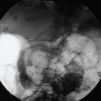

Fig. 1. Prótesis de Wallstant inicial obstruida sobre la que se insertó endoscópicamente una segunda prótesis más larga.